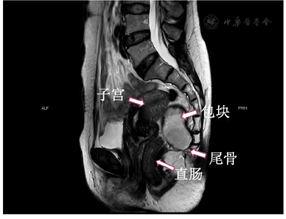

患者前期体检通过经阴道子宫附件彩超发现盆腔包块,后于我院行盆腔MRI检查,考虑骶尾部囊肿,妇检可扪及盆腔包块。

骶尾部畸胎瘤的诊断主要依靠CT和MRI,MRI对软组织的分辨率较高,对于肿瘤良恶性的鉴别有一定的参考价值,同时可以协助临床医师判断肿瘤的侵犯范围以及其与周围组织结构的关系[2,9]。α-胎蛋白(AFP)、癌胚抗原(CEA)、人类绒毛膜促性腺激素(HCG)和乳酸脱氢酶(LDH)等血清肿瘤标记物的升高通常提示恶性转化可能[2,5,10]。

本例患者术前经阴道彩超发现盆腔包块,考虑为附件来源,进一步行MRI检查发现包块位于直肠旁,因此MRI在鉴别诊断中起到了至关重要的作用,这给我们为患者制定治疗方案提供了可靠依据。